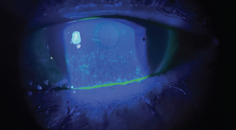

Fortunately, the toolbox of aesthetic ocular technologies continues to grow. In-office devices such as intense pulsed light, radiofrequency, gland heating and clearing systems, and low-level light therapy are transforming the way we approach both OSD and ocular aesthetics. These technologies treat the root causes of disease while improving periocular appearance. They reduce inflammation, restore lid function, and minimize signs of fatigue and aging. Moreover, they offer optometrists a unique opportunity to diversify their practice offerings while delivering outcomes that resonate with their patients’ desires.